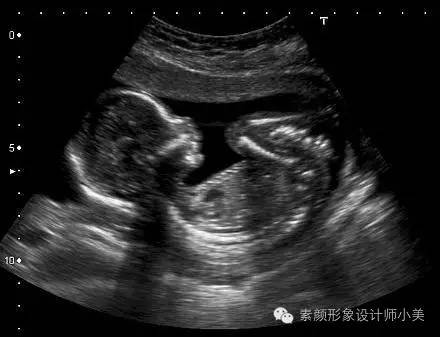

27周的胎儿现在体重已有900克左右,身长大约达到38厘米。可以看到胎儿头上已长出了短短的胎发。这时胎儿的听觉神经系统也已发育完全,对外界声音刺激的反应更为明显。你可以继续为他讲故事或者给他听音乐,这会让你和胎儿都感到平静和愉快。